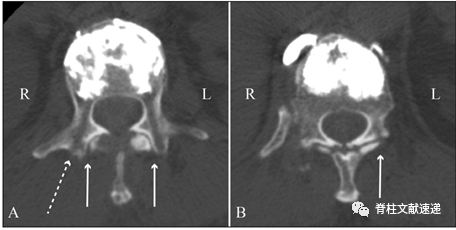

图注:图A为PKP术后CT结果显示PKP孔道未累及椎间小关节;图B显示PKP孔道累及左侧椎间小关节;